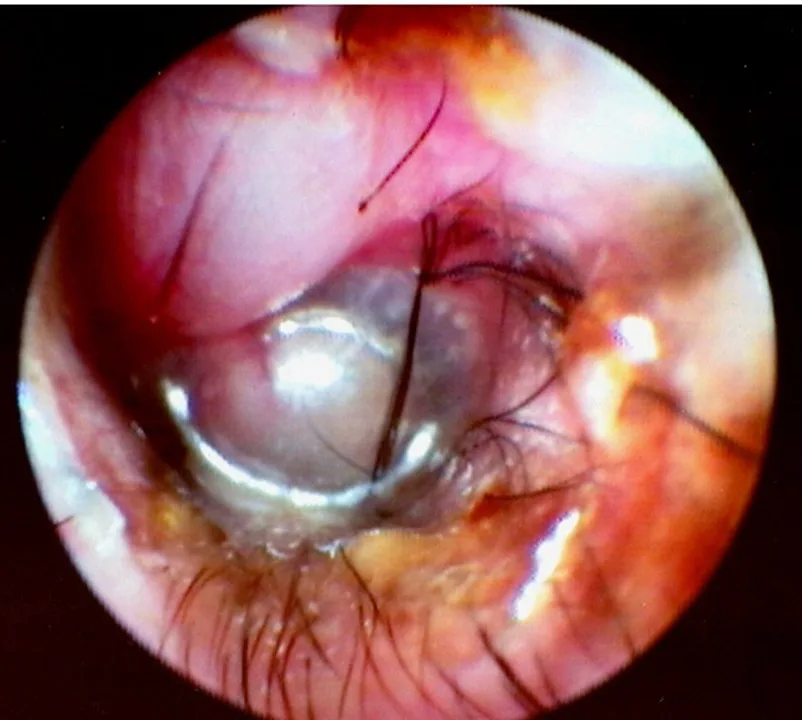

Bulging eardrum identified on otic examination (Figure 1)

FIGURE 1 Middle ear exudates fill tympanic bulla, putting painful pressure on the eardrum and causing it to bulge outward.